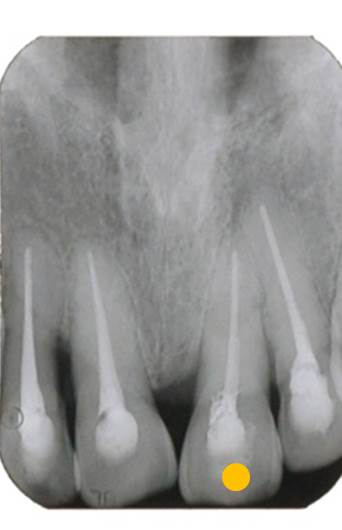

次にレントゲン撮影をします。

このレントゲンで分るのは、神経を取った歯ということです。神経を取った歯は、歯の芯の部分に薬が入っています。よく「歯医者で神経取った」と言われます。歯の中には、神経だけでなく血管が存在します。「神経を取る」というのは、「神経も血管も取る」ということなのです。歯の中の血管を取ってしまえば、白血球が存在しなくなります。神経や血管を取った際に、歯の中に細菌が残ってしまえば後から膿んでくる可能性が非常に高くなるのです。

ですから、できるだけ「神経」は取らない方が良いのです。

※参考に、下図の写真は神経や血管を取っていない歯のレントゲン写真です。歯の中に材料が入っていないのが分ります。つまり、神経のある歯は血が通っていて白血球が警備してくれているため、絶対に膿んでくることはないのです。